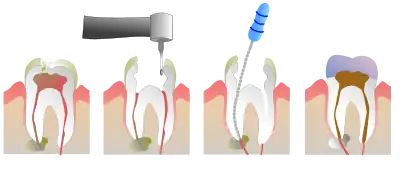

Root canal treatment (also known as endodontic therapy, endodontic treatment, or root canal therapy) is a treatment sequence for the infected pulp of a tooth that is intended to result in the elimination of infection and the protection of the decontaminated tooth from future microbial invasion. It is generally done when the cavity is too big for a normal filling.[1] Root canals, and their associated pulp chamber, are the physical hollows within a tooth that are naturally inhabited by nerve tissue, blood vessels and other cellular entities.[2]

Endodontic therapy involves the removal of these structures, disinfection and the subsequent shaping, cleaning, and decontamination of the hollows with small files and irrigating solutions, and the obturation (filling) of the decontaminated canals. Filling of the cleaned and decontaminated canals is done with an inert filling such as gutta-percha and typically a zinc oxide eugenol-based cement.[3] Epoxy resin is employed to bind gutta-percha in some root canal procedures.[4] Another option is to use an antiseptic filling material containing paraformaldehyde like N2.[5] Endodontics includes both primary and secondary endodontic treatments as well as periradicular surgery which is generally used for teeth that still have potential for salvage.[6][7]

Treatment procedure

The procedure is often complicated and may involve multiple visits over a period of weeks.

If a tooth is considered so threatened (because of decay, cracking, etc.) that future infection is considered very likely or inevitable, a pulpectomy (removal of the pulp tissue) is advisable to prevent such infection. Usually, some inflammation and/or infection is already present within and/or below the tooth. To cure the infection and save the tooth, the dentist drills into the pulp chamber and removes the infected pulp. To eliminate bacteria from the pulp chamber and root canals, the use of efficient antiseptics and disinfectants is necessary.[10] The soft tissues are either drilled out of the root canal(s) with engine driven rotary files, or with long needle-shaped hand instruments known as hand files (H files and K files).

Opening in the crown

The endodontist makes an opening through the enamel and dentin tissues of the tooth, usually using a dental drill fitted with a dental burr.

Removal of pulp tissue

Filling the root canal